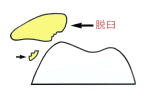

膝蓋骨脱臼の概説

膝蓋骨脱臼の進行や軟骨障害

膝蓋骨脱臼で初回脱臼後10年以上になると、脱臼力も強くなり軟骨の障害例が多くなります。軟骨障害が進むと元通りに回復させることは難しく脱臼は治っても軟骨の痛みが残りますので早めに手術を受けて下さい。初回の脱臼の平均は14~18歳頃ですので手術せずに30歳代になるとこのような状態になります。